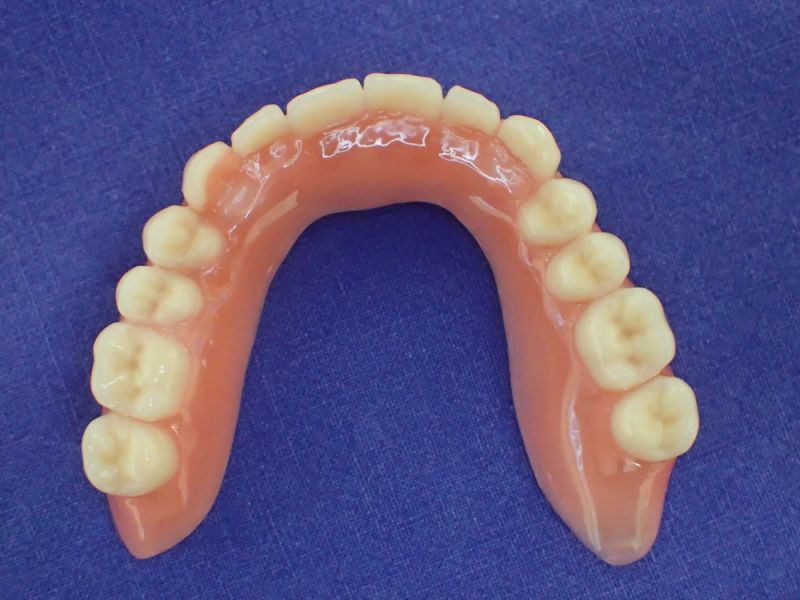

Nach inzwischen 12 jähriger Tragedauer wurden alle Kunststoffteile erneuert, das metallische Grundgeroüst der Arbeit erhalten und die Arbeit befindet sich in einem Zustand, der sich weitgehend an der Ersterstellung orientiert.

Bei derartigen Arbeiten ist es tatsächlich möglich grundlegende Konstruktionsmerkmale einer alten Arbeit zu übernehmen und Verschleißteile aus Kunststoff zu erneuern.

Im Prinzip ist das beliebig oft möglich und für den Patienten mit einer enormen Kostenersparnis verbunden.

Entscheidend ist hierbei, dass schon bei der Ausgangskonzeption, wenn die Überlegungen der Art der Versorgung, der Art der Verankerungselemente Überlegungen angstellt werden: "Was passiert wenn?